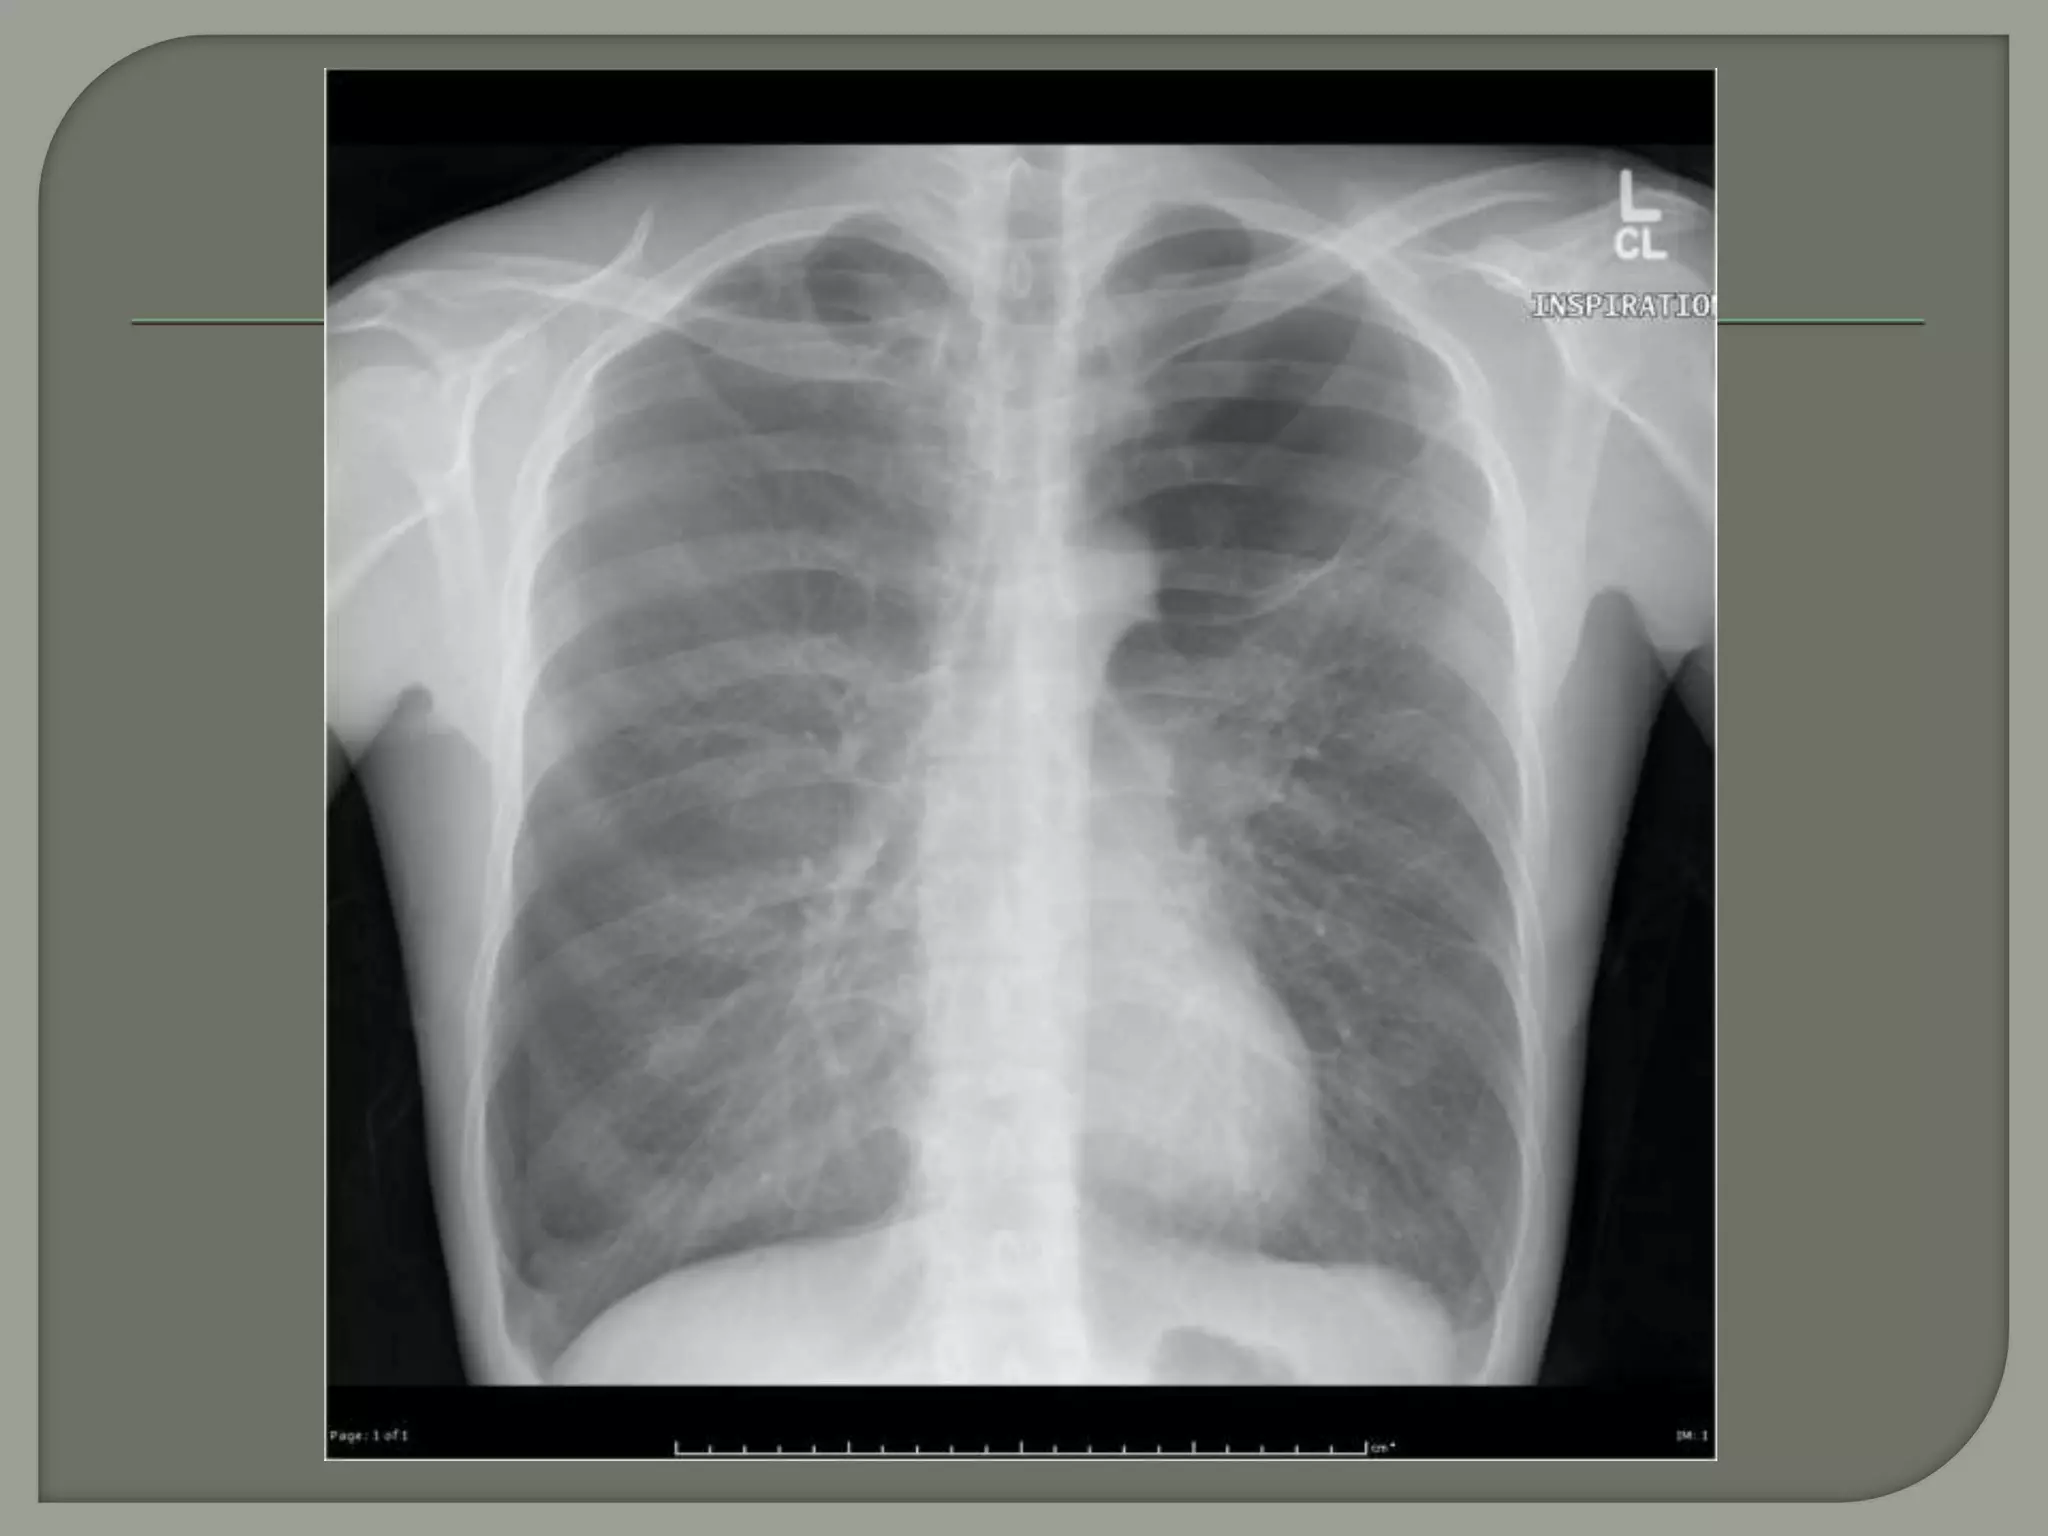

 In asymptomatic individuals, bullae may be detected in the

course of routine chest radiography. Small bullae rarely

become visible on the chest radiograph but are usually

easily visible by CT. As a rule, small bullae usually produce

no symptoms, signs, or discernible alterations in pulmonary

function.